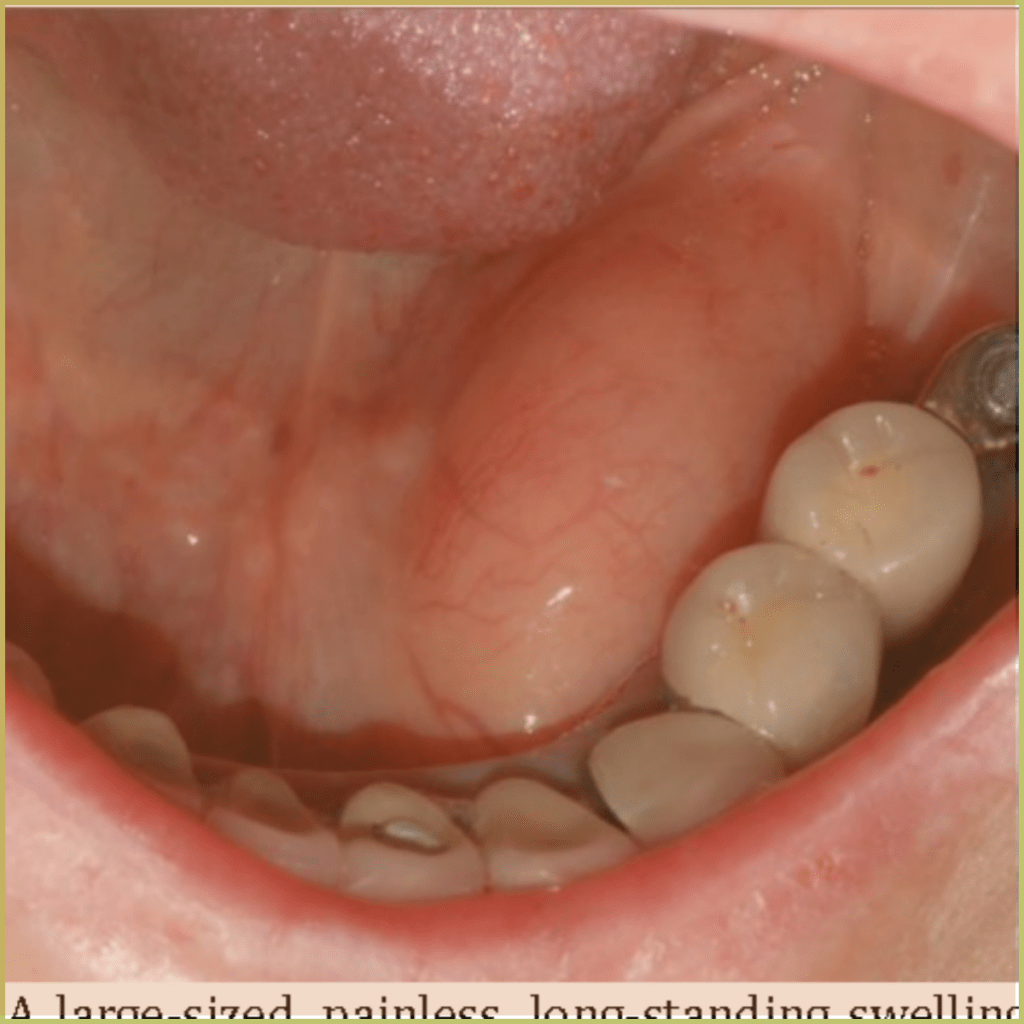

LIPOMA

A lipoma is a benign tumor made of adipose tissue. The etiology is generally unclear, but risk factors include family history, obesity, and trauma. The common clinical presentation includes:

- Asymptomatic, slow-growing well circumscribed nodular lesion.

- Sessile or pedunculated base.

- Soft and fluctuant with dough-like consistency.

- Most common sites include buccal mucosa and tongue.

- May have a yellowish tinge if superficially located.

- Larger lesions often are covered by telangiectatic vessels.